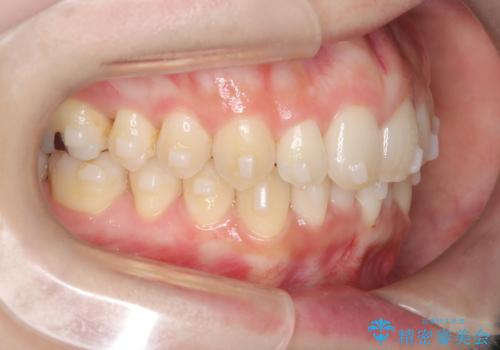

- 患者様は、上下前歯の歯列不正(ガタガタ)を主訴としてご来院されました。治療計画として、透明なマウスピース型矯正装置「インビザライン」を使用し、約2年の期間を見込んで前歯部の歯列を整える方針を立てました。特に下顎前歯に歯肉退縮のリスクがあるため、治療中にIPR(インタープロキシマルリダクション)を行い、歯間を適切に削ることで、過度な圧力を避け、歯肉退縮を防ぎながら配列を進めました。治療は慎重に進め、最終的にきれいで整った前歯の歯並びを目指しました。

インビザラインによる矯正治療は、患者様自身が装着するマウスピース型の装置を使用するため、装着時間の徹底が重要です。特に、下顎前歯の歯肉退縮を避けるため、IPRを施すことで歯間スペースを確保し、歯肉にかかる負担を減らしました。この方法により、歯並びを整えながらも歯肉の健康を保つことができます。治療期間中は定期的にチェックを行い、歯肉の状態や歯の動きを慎重に確認しました。また、治療後はリテーナーを装着して歯並びを維持し、安定させました。